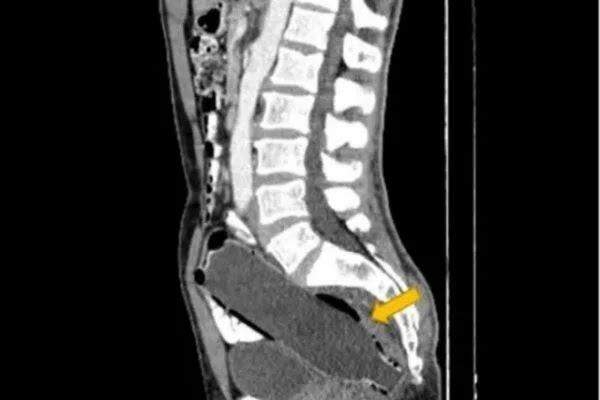

image garrafa presa no intestino apareceu em resultado de exame (Reprodução)

O homem de 50 anos foi submetido a uma tomografia computadorizada, que mostrou a garrafa de 250 ml alojada em seu intestino. Ele teria enfiado o objeto por conta própria, mas não conseguiu removê-lo. Dessa forma, a garrafa chegou a atingir o intestino grosso do homem.